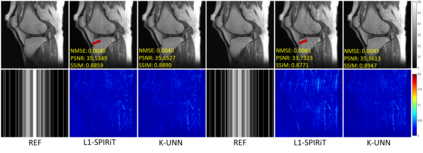

Recently, untrained neural networks (UNNs) have shown satisfactory performances for MR image reconstruction on random sampling trajectories without using additional full-sampled training data. However, the existing UNN-based approach does not fully use the MR image physical priors, resulting in poor performance in some common scenarios (e.g., partial Fourier, regular sampling, etc.) and the lack of theoretical guarantees for reconstruction accuracy. To bridge this gap, we propose a safeguarded k-space interpolation method for MRI using a specially designed UNN with a tripled architecture driven by three physical priors of the MR images (or k-space data), including sparsity, coil sensitivity smoothness, and phase smoothness. We also prove that the proposed method guarantees tight bounds for interpolated k-space data accuracy. Finally, ablation experiments show that the proposed method can more accurately characterize the physical priors of MR images than existing traditional methods. Additionally, under a series of commonly used sampling trajectories, experiments also show that the proposed method consistently outperforms traditional parallel imaging methods and existing UNNs, and even outperforms the state-of-the-art supervised-trained k-space deep learning methods in some cases.